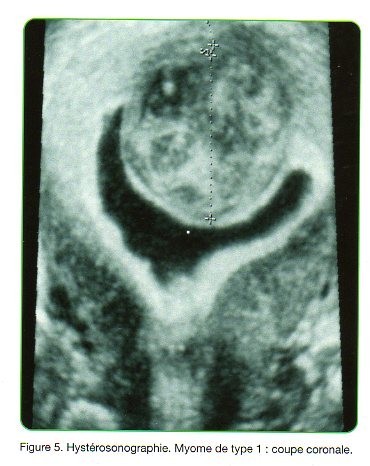

les images sont issues de l'article "classification échographique des myomes" de JM LEVAILLANT, H FERNANDEZ, G LEGENDRE paru en décembre 2012 dans Gynécologie et Obstétrique Pratique.

Hysteroscopie